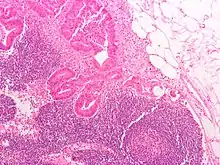

Histology of a normal lymphoid follicle, showing dark, light, mantle and marginal zones

A lymph node is divided into compartments called nodules (or lobules), each consisting of a region of cortex with combined follicle B cells, a paracortex of T cells, and a part of the nodule in the medulla.[15] The substance of a lymph node is divided into the outer cortex and the inner medulla.[3] The cortex of a lymph node is the outer portion of the node, underneath the capsule and the subcapsular sinus.[15] It has an outer part and a deeper part known as the paracortex.[15] The outer cortex consists of groups of mainly inactivated B cells called follicles.[4] When activated, these may develop into what is called a germinal centre.[4] The deeper paracortex mainly consists of the T cells.[4] Here the T-cells mainly interact with dendritic cells, and the reticular network is dense.[16]

The medulla contains large blood vessels, sinuses and medullary cords that contain antibody-secreting plasma cells. There are fewer cells in the medulla.[4]

The medullary cords are cords of lymphatic tissue, and include plasma cells, macrophages, and B cells.